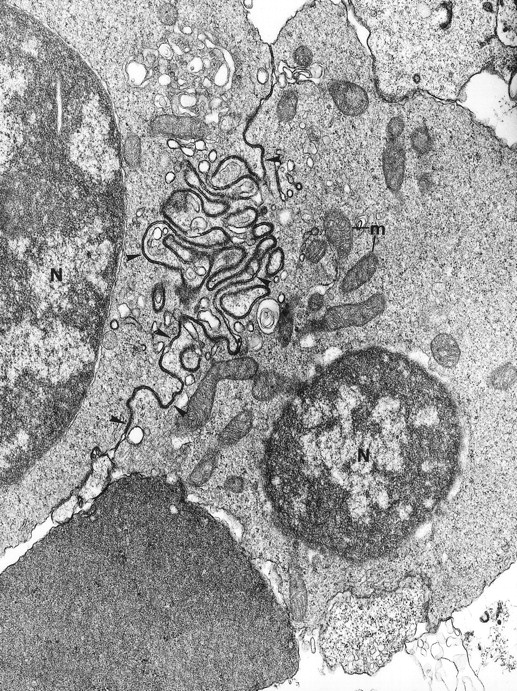

Fig. 2.

The electron microscopic aspect of the bone marrow erythroblasts from patient 1: Cells are joined by interdigitating processes of the plasma membrane (arrowheads). They delineate areas of cytoplasm which are deprived of ribosomes (N, nucleus; m, mitochondria). Original magnification: ×21,000.

Electron microscopy confirmed the diagnosis of erythroblastic synartesis in the 3 patients. Plasma membranes of adjacent erythroblasts were joined by closely interdigitating processes (Fig2). Cytochemical demonstration of the peroxidatic activity of hemoglobin (not shown) allowed identification of maturation stages of the erythroblasts, because its level of intensity relates to the hemoglobin content of each cell. This technique showed that erythroblasts of the same maturation stage, as well as those of different maturation stages, were linked. Ribosomes were absent at sites of linkage via interdigitating process, corresponding with the nonbasophilic areas observed by light microscopy (Fig3a). At the junction sites, coated pits and rhopheocytosis vesicles were absent, probably because a macrophage expansion would find it impossible to penetrate this zone of tightly linked plasma membrane. Ferritin granules were never observed within these junctions. Junctions between erythroblasts had a characteristic morphology: resembling gap junctions, they were formed by 2 closely placed membranes joined by periodical structures every 150 Å, giving rise to a zipper-like appearance (Fig 3b). Isolated normoblasts often displayed picnotic nuclei and/or binuclearity. The 2 external leaflets of the plasma membrane of adjacent erythroblasts were separated by a constant space of 145 Å in patient 1, and 180 Å in patients 2 and 3.